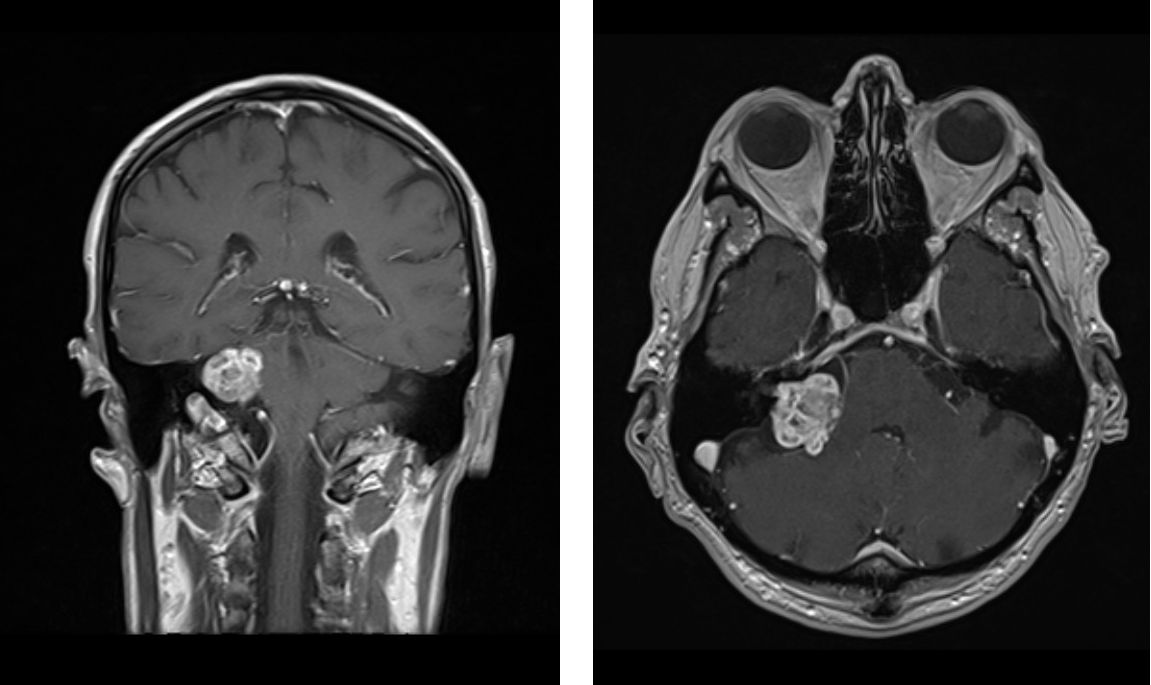

MRT des Gehirns

Operationen an Vestibularisschwannomen können zu Fazialisparesen führen.